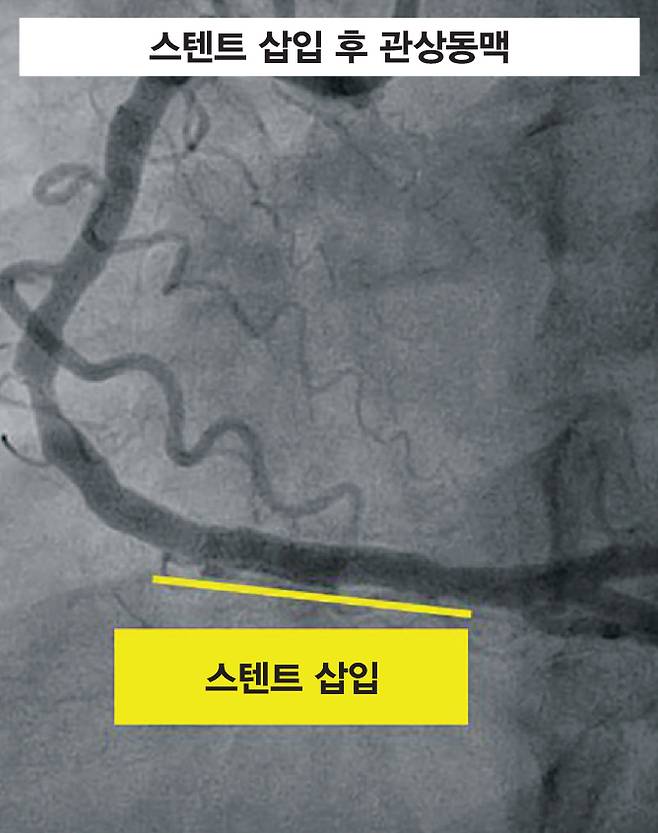

혈관이 심하게 좁아진 불안정형 협심증이나 심근경색인 경우는 응급으로 경피적 관상동맥중재술(PCI)이 필요하다. 흔히 '스텐트 시술'이라 불리는 이 치료법은 허벅지(대퇴동맥)나 손목(요골동맥)을 통해 기구를 넣어 심장까지 도달한 뒤, 풍선으로 막힌 부위를 넓히고 스텐트(그물망)를 삽입해 혈관이 다시 좁아지지 않도록 한다. 최근에는 손목을 통한 시술이 늘어나고 있는데, 이는 시술 후 출혈 위험을 줄이고 회복을 빠르게 한다는 장점이 있다. 스텐트 시술은 막힌 부위가 한 곳일 때 유리하며, 시술 시간이 짧고 회복이 빠른 장점이 있다.